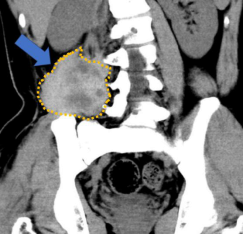

近日,南方医院创伤骨科骨软组织肿瘤亚专业组与介入科通力合作,成功完成了该院首例经皮微创硬纤维瘤冷冻消融术。经过术前缜密规划设计,在C臂CT引导下,在局麻下,进行了髂腰部硬纤维瘤的冷冻消融。手术过程顺利,术后影像显示疗效满意,患者隔天即顺利出院。

硬纤维瘤是一种常见的侵袭性中间性软组织肿瘤,手术复发率很高,无有效治疗药物,是国际公认的治疗难题。该青少年患者8年间经历南方医院和中山一院两次手术,并尝试了靶向药物,均复发难以控制。基于我院骨软组织肿瘤亚专业在开放性冷冻消融十余年的临床应用经验,经科室余斌主任组织讨论,决定针对该患者采用影像引导、经皮冷冻消融技术。

图1 术前CT:黄色虚线边框示硬纤维瘤大小